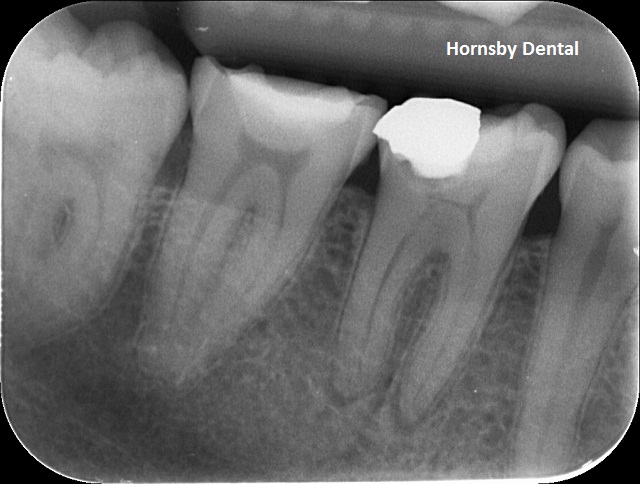

PRE-OP

Pre-op: Deep decay underneath old restoration. Previously un-monitored and the tooth was in excruciating pain. Large shadow underneath the opaque white mass is the decay, and at tip of the tooth root is a dark shadow which suggests a zone of infection. The tooth can be saved with a carefully performed root canal therapy and avoid the loss of the tooth.